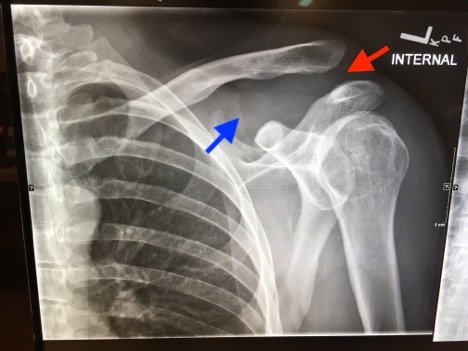

Plain films of the left shoulder showed elevation of the left clavicle above the acromion. There was an increase in the acromioclavicular (AC) and coracoclavicular (CC) distances (increased joint distances marked with red and blue arrows, respectively). A normal AC joint measures 1-3 mm whereas a normal CC distance measures 11-13 mm.1 The injury was classified as a Rockwood type III AC joint separation.

Initial evaluation with imaging includes plain films with three views: the anterior-posterior (AP) view with the shoulder in internal and external rotation as well as an axillary, or scapula-Y view (sensitivity 40%, specificity 90% for all films).6,7 AC joint injuries are classified by the Rockwood system.8 Type I involves a sprain or incomplete tear of the AC ligaments with an intact CC ligament. The AC joint appears normal on X-ray, but can become widened with stress, achieved by having the patient hold a 10-15 pound weight from each forearm.1,9 Type II injuries involve a torn AC ligament, disrupting the AC joint. The AC joint appears widened on radiographs.1,9 The AC and CC ligaments are disrupted in type III injuries with an increased CC distance of 25%-100% on plain films.1,10 In addition to torn AC and CC ligaments, the clavicle is posteriorly displaced in a type IV injury. Because the AP film may not reveal the posterior displacement of the clavicle, the axillary view is vital for correct classification of type IV injuries.1 A type V injury involves disruption of the AC and CC ligaments as well as torn muscle attachments of the trapezius and deltoid on the clavicle and scapula, leading to greater AC joint displacement on radiographs. The CC distance appears 100%-300% greater than normal.1,10 Type VI injuries are caused by a direct blow to the superior surface of the clavicle resulting in inferior displacement. On X-ray, the lateral end of the clavicle is inferior to the acromion and coracoid processes in Type VI injuries.1